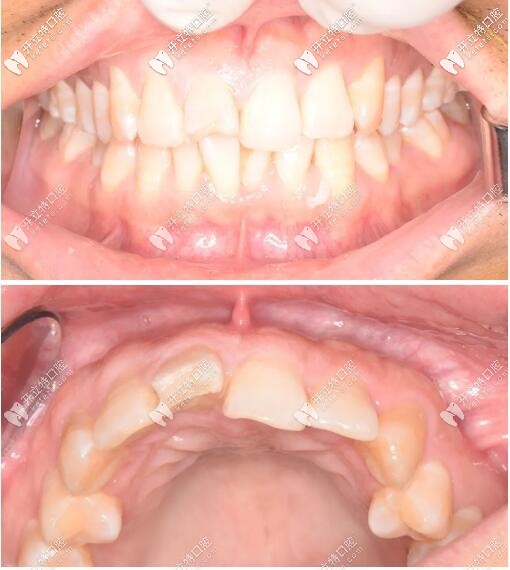

三周后戴入全瓷修復(fù)體,紅白美學(xué)效果理想;

門牙瑞士iti鈦親水4.1mm*10mmBL種植體修復(fù)案例

戴牙一年后復(fù)診,口內(nèi)正面觀及側(cè)面像。

門牙磕傷瑞士iti種牙修復(fù)1年后